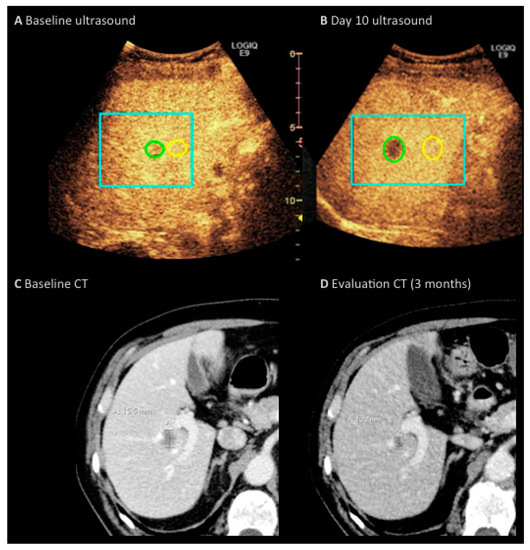

Dynamic Contrast-Enhanced Ultrasound of Colorectal Liver Metastases as an Imaging Modality for Early Response Prediction to Chemotherapy

2.2. Imaging Protocol

2.3. Imaging Analysis